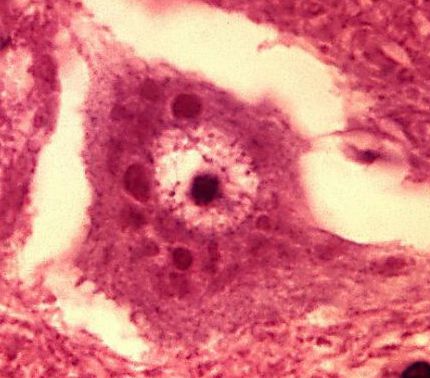

Which virus/viral family will have cytoplasmic, eosinophilic inclusions within neuronal cells? _____